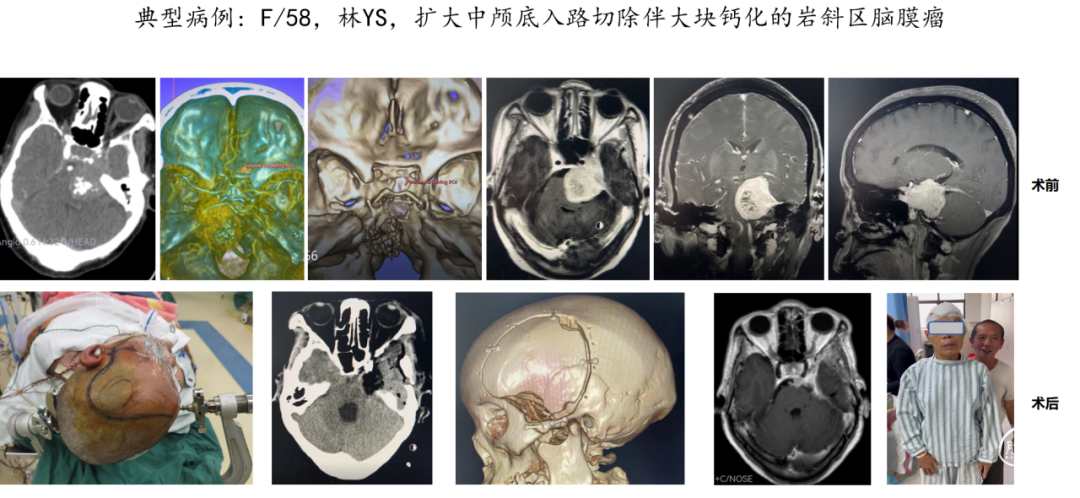

“双镜联合”是一种先进的神经外科手术技术,它结合了显微镜和神经内镜的优势,旨在更安全、更精准地切除位于颅底复杂区域的肿瘤,这是我科近几年开展的院内新技术,这种手术方法在处理如岩斜区、海绵窦区、枕骨大孔区、颈静脉孔区等难以到达且手术风险高的区域时,具有显著的优势。